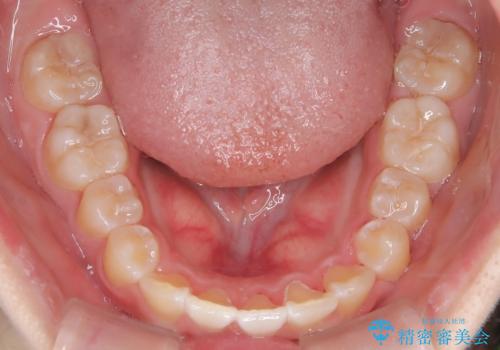

【インビザライン】前歯を下げたい

今回は遠心移動とIPRによってここまで前歯を下げることができました。

- 前歯が出ていることを主訴に来院されました。

インビザラインにて奥歯の遠心移動を行いながら最大限前歯が下がるように治療を行いました。